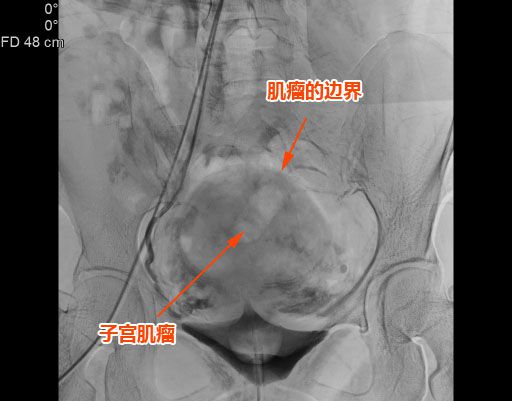

△子宮肌瘤巨大,邊界清晰。

該名患者來自揭西,有下腹痛1個多月,腹部外觀像孕婦,經影像學檢查可見子宮前壁肌間有1個7.5cm左右的巨大肌瘤。此類患者如采用腹腔鏡或傳統手術治療,需要做子宮切除手術。患者因年紀僅40餘歲,相對較輕,想要保住子宮。